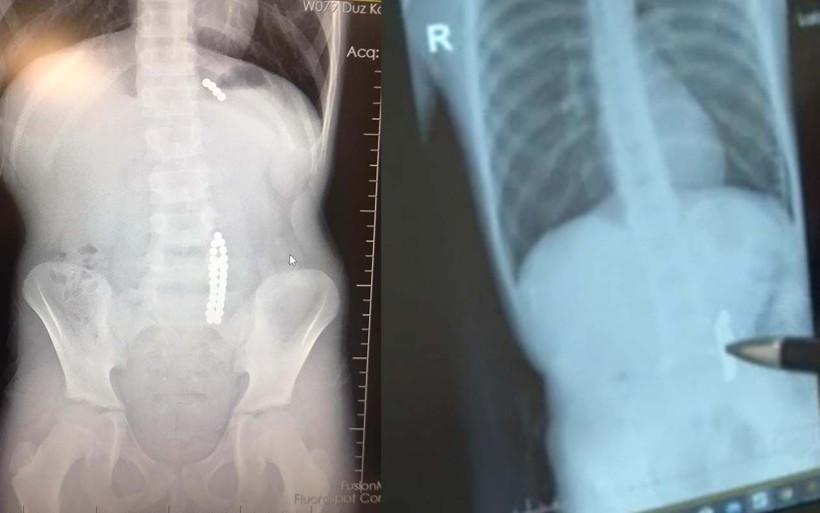

İstanbul Beylikdüzü’nde kusma karın ağrısı şikayetiyle hastaneye getirilen 9 yaşındaki çocuk çocuğun röntgen filmi çekilince gerçek ortaya çıktı. Oyuncak olarak satılan stres bilyeleri olarak da bilinen neodyum adlı güçlü mıknatıstan 42 adet bağırsağında tespit edildi. Ameliyata alınan çocuğun delinen bağırsağından mıknatıslar çıkarıldı.

Birkaç gün sonra şiddetli karın ağrısı ve kusma şikayeti ile hastaneye gelen çocuğun röntgeni çekildi.

Röntgen filminde çocuğun midesinde boncuklar halinde yabancı bir cisim tespit edildi.